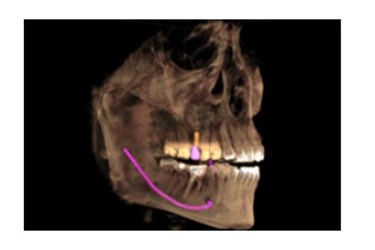

Dr. Ronald Receveur, who provides comprehensive New Albany cosmetic dental work, has written a blog championing the use of 3-D scanning technology in placing dental implants. Dr. Receveur uses a 3-D CAT scan machine to better assess patients’ dental needs and to map out complicated dental procedures like All On 4 dental implants at his New Albany contemporary dental implant center.

Dr. Receveur uses a 3-D CAT scan machine to better assess patients’ dental needs and to map out complicated dental procedures like All On 4 dental implants at his New Albany contemporary dental implant center.

“Typical dental offices do not offer 3-D imaging. In fact, that typically requires a visit to your local hospital,” Dr. Receveur said. “At our office, we don’t ask our patients to travel all across town for treatment. We want to provide the best care possible in one location.”

The 3-D imaging is part of Dr. Receveur’s One Day Smile Solution, a method the New Albany dentist uses to give patient’s dental implants in one day or to complete multiple treatments in one day with the aid of IV sedation.

“Our 3-D imaging is the bedrock of our One Day Smile Solution,” Dr. Receveur said. “This technology increases our efficiently by providing the most accurate image of the patient’s oral cavity, down to the smallest blood vessel.”